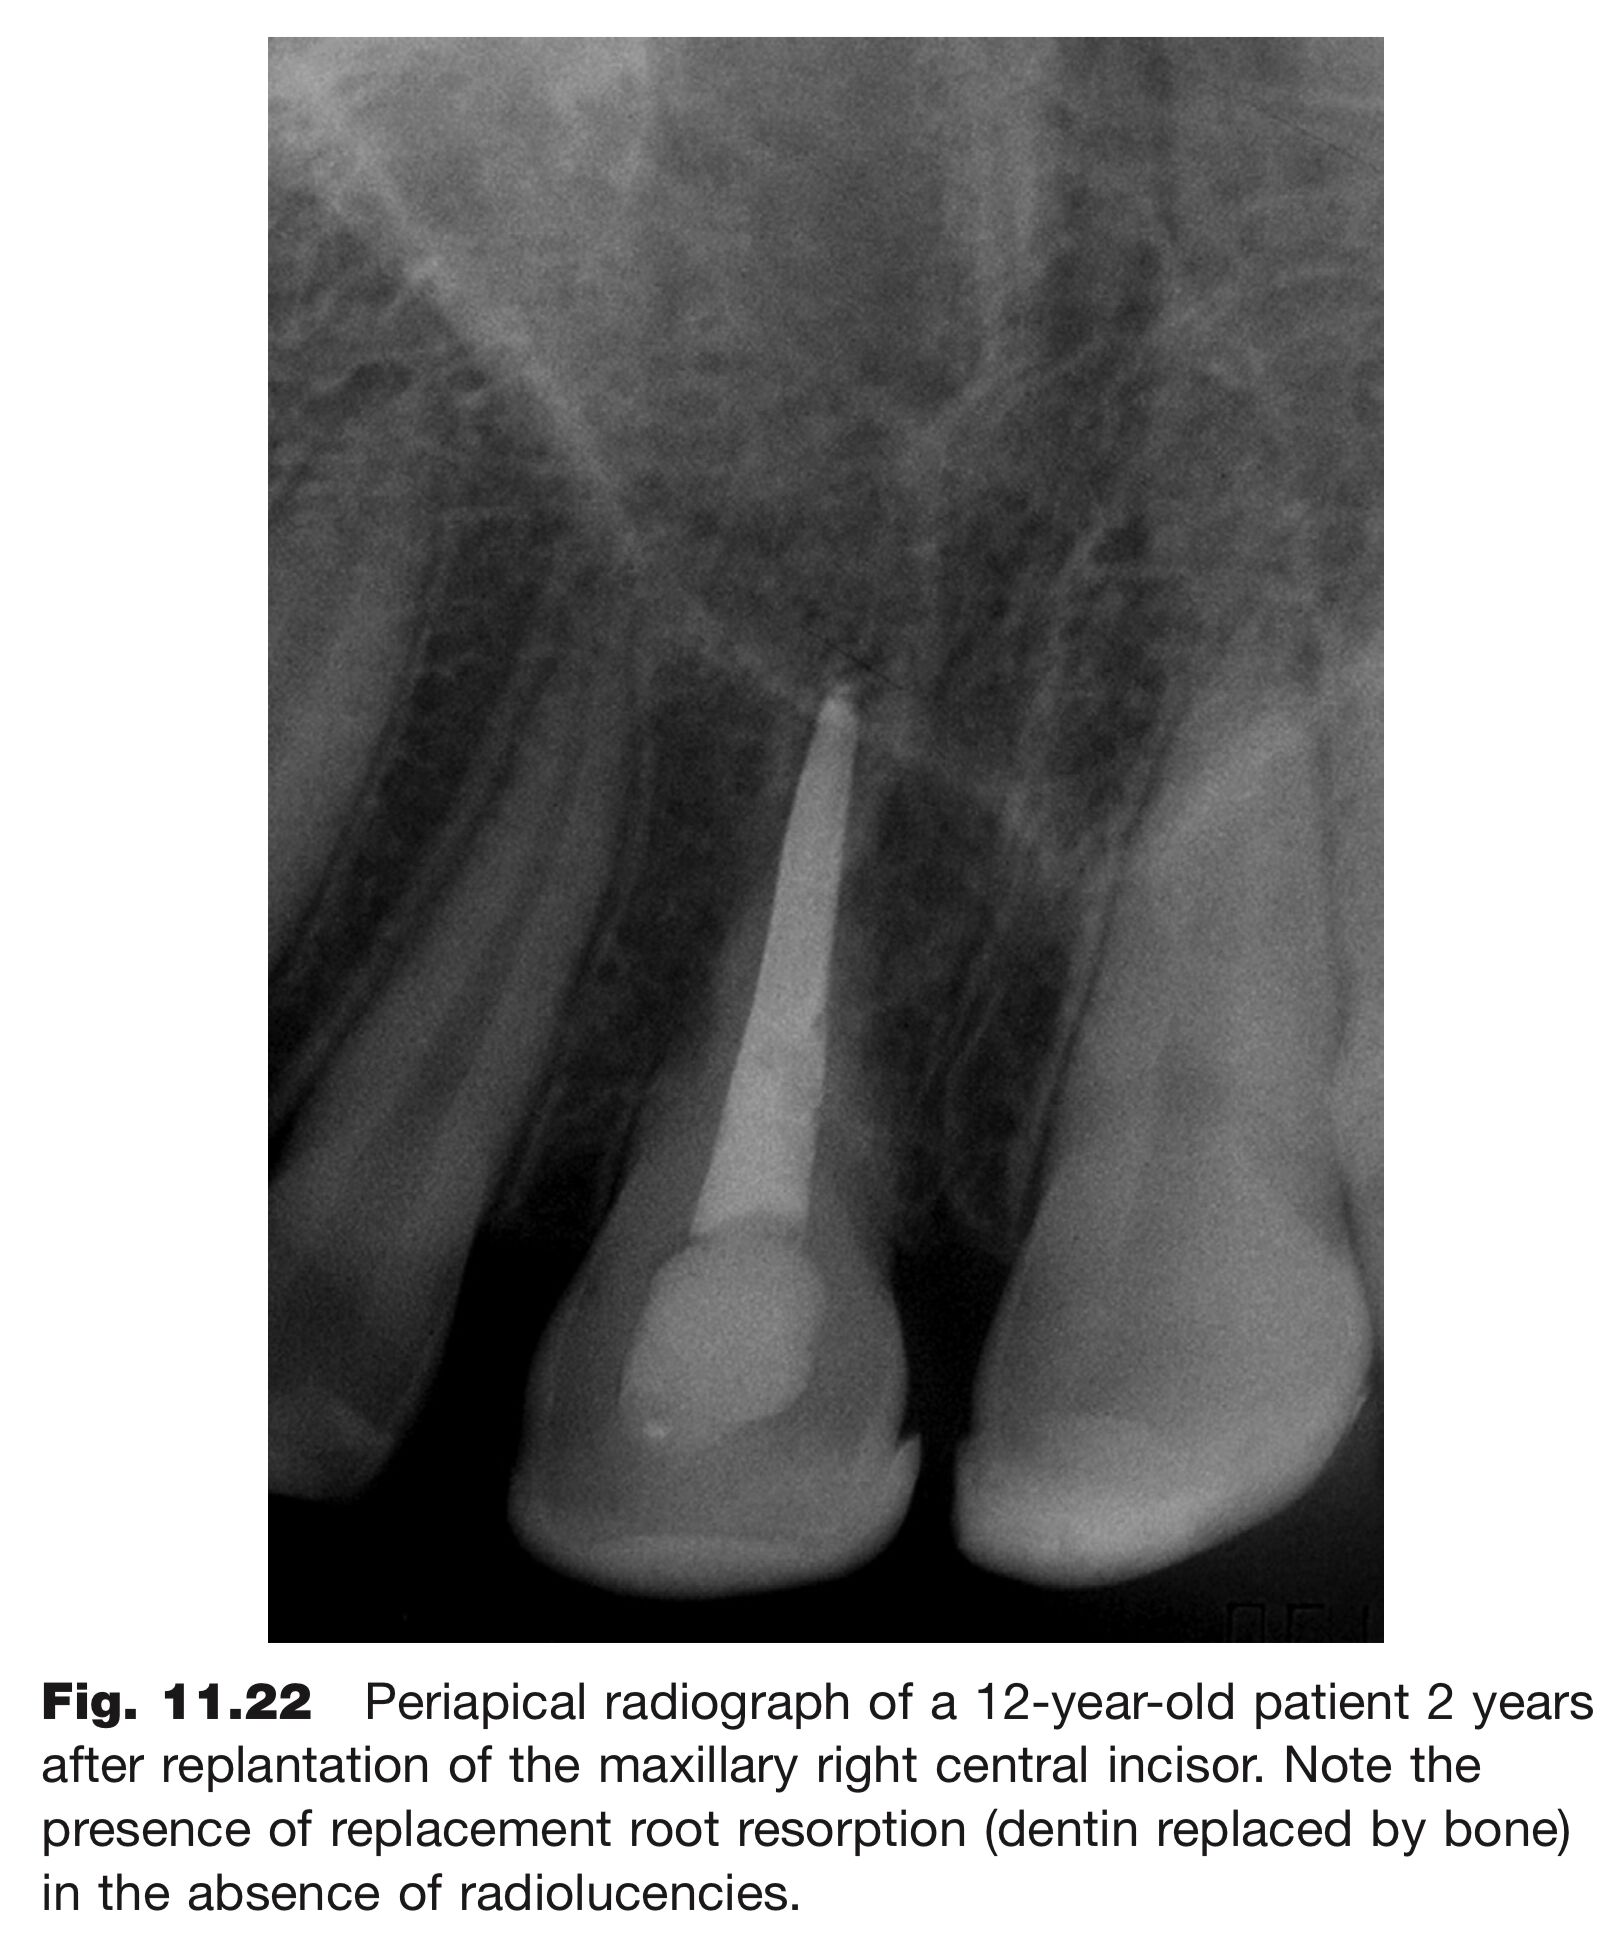

(D)X光影像上,牙根吸收處仍可見到牙周韌帶